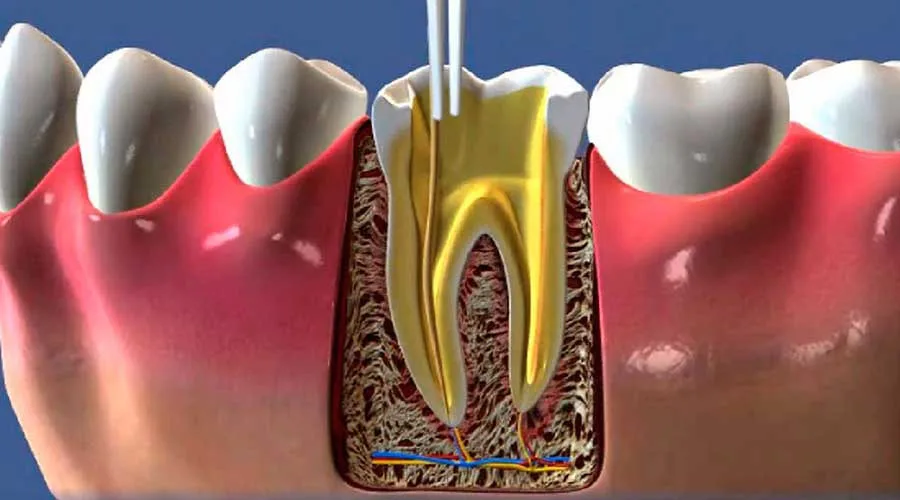

O foco principal é remover a fonte da infecção de maneira segura e protegida. Ao tratar o canal, o dentista impede a propagação de bactérias que poderiam afetar outros dentes e a gengiva, mantendo o equilíbrio da boca.

Tecnologias Avançadas: Uso de instrumentação rotatória e localizadores apicais para maior eficácia;

A infraestrutura disponível na capital permite que o procedimento seja nítidamente mais rápido e confortável. O uso de microscopia e materiais de alta fidelidade assegura uma desinfecção profunda e duradoura da região.

Durante o procedimento, o dentista realiza a anestesia da área para remover a polpa inflamada e limpar os canais radiculares.